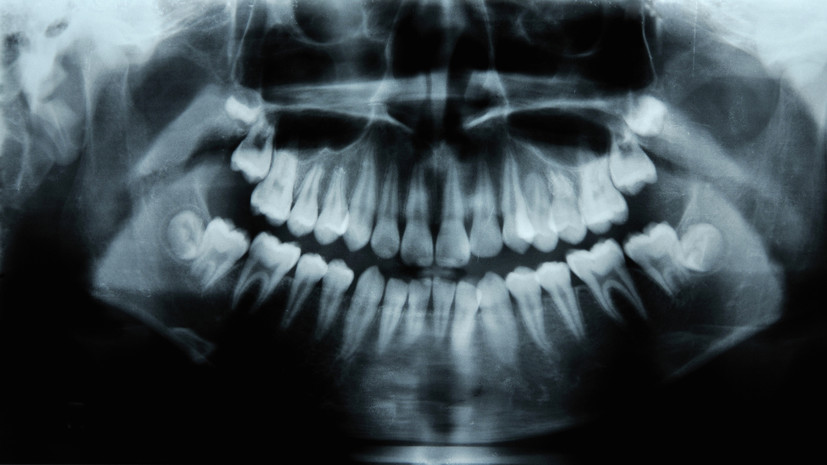

Врач Серёгина: отказ от лечения зубов может привести к проблемам с сердцем

В беседе с РИАМО эксперт отметила, что чаще всего запущенный кариес захватывает внутренний слой зуба (дентин) и приближается к пульпе — нервно-сосудистому пучку внутри зуба.

По словам специалиста, далее инфекция может распространиться на корень зуба и костную ткань вокруг неё.

После чего инфекция из полости рта может попасть с током крови и вызвать инфекционный эндокардит — воспаление клапанов сердца, добавила врач.